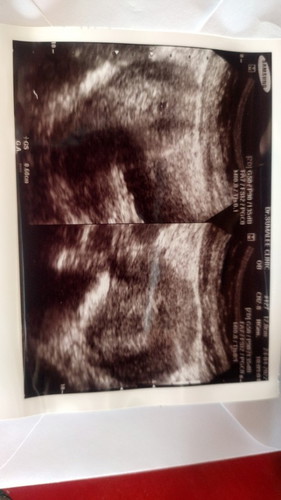

ท้องอ่อนๆ วันนี้มีอาการหน่วงท้อง แล้วมีเลือดออกนับอายุครรภ์ตอนนี้ได้ประมาณ6wไปหาหมอคลีนิคซาวด์ดูหมอ

บอกเล็กมากรอดูอาการว่าจะอยู่หรือไป#ขอคำแนะนำหน่อยค่ะ